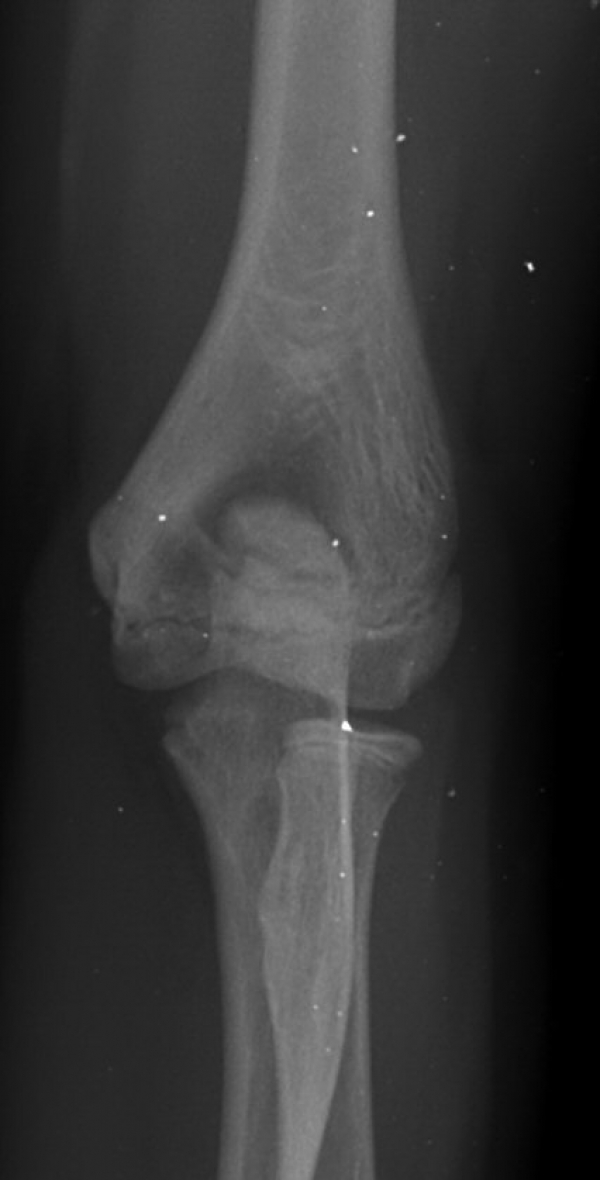

´Ü¼ø¹æ»ç¼±°Ë»ç

ÆÈ²ÞÄ¡ ³»»ó°ú ¿ÜÃø¿¡ ¹Ì¼¼ÇÑ °ñÆíÀÌ °üÂû µÊ(±×¸² 7).